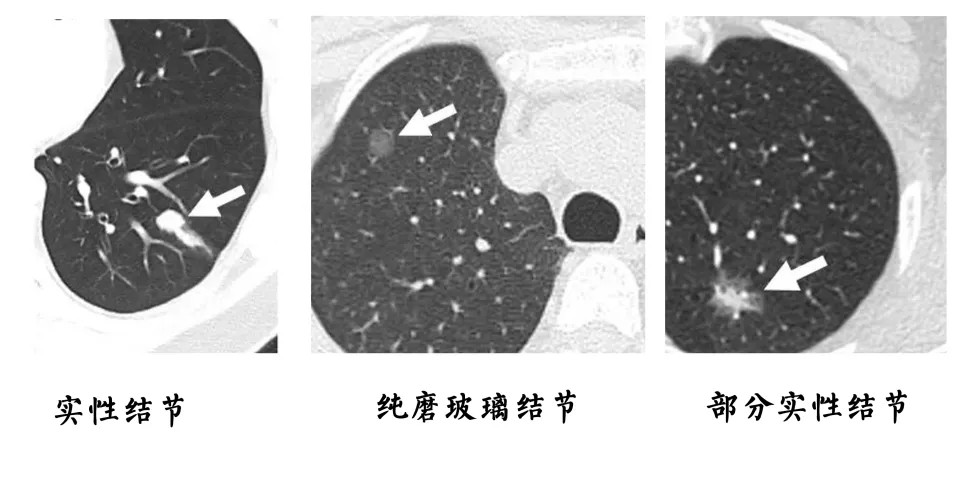

医学影像学:肺结节,几种常见良性病变,正常结构及小肺癌表现